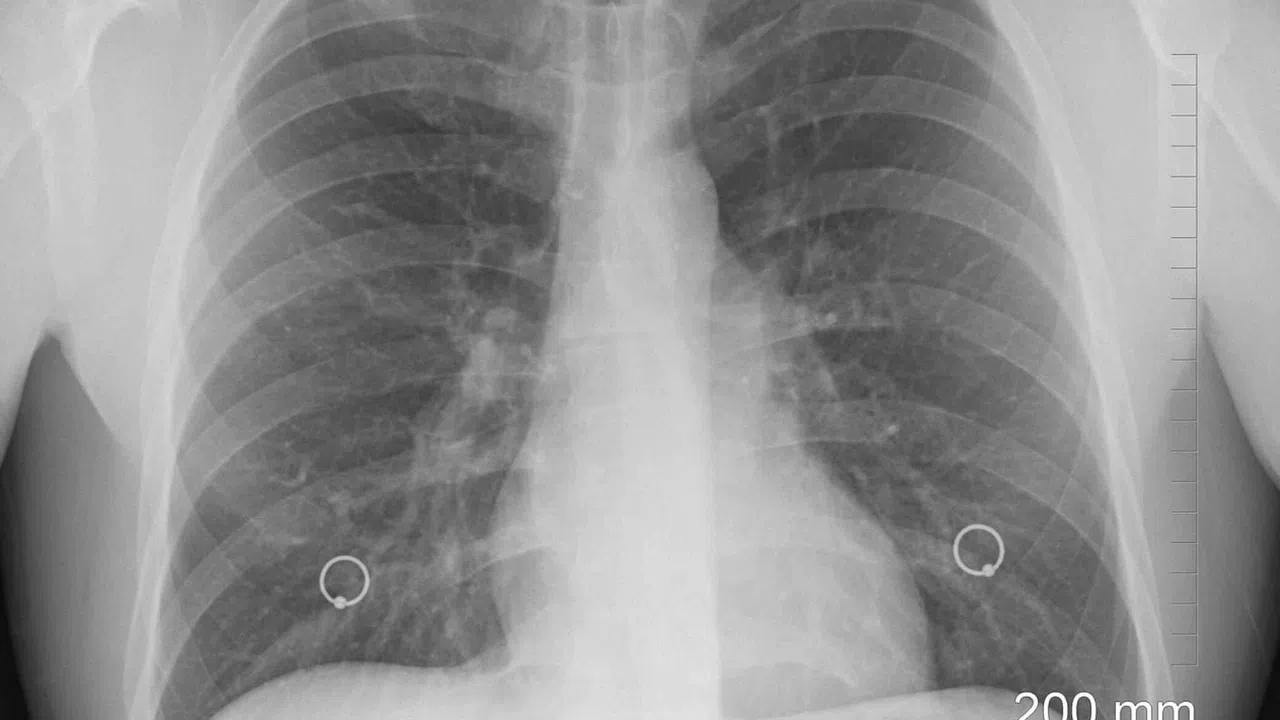

Dünya genelinde kansere bağlı ölümlerin en sık nedeni olan akciğer kanseri, her yıl milyonlarca insanın hayatını kaybetmesine yol açıyor. Bayındır Söğütözü Hastanesi Göğüs Hastalıkları Bölüm Başkanı Doç. Dr. Cem Gündoğdu, yaptığı açıklamada akciğer kanseri nedeniyle yaşanan ölümlerin tüm kanser ölümlerinin yaklaşık beşte birini oluşturduğunu belirtti. Gündoğdu, hastalığın en büyük nedeninin sigara kullanımı olduğunu vurgulayarak, vakaların %85-90'ının sigara ile ilişkili olduğunun altını çizdi.

Sigaradan bağımsız olarak çevresel ve genetik etkenlerin de akciğer kanserine yol açabildiğini belirten Gündoğdu, ailede akciğer kanseri öyküsü, asbest ve radon gazına maruziyet, hava kirliliği gibi faktörlerin riski artırdığını söyledi. Hastalığın erken dönemde belirti vermediğine dikkat çeken Gündoğdu, "Geçmeyen öksürük, göğüs ağrısı, kanlı balgam, nefes darlığı gibi bulgular önemli. İleri evrede baş ağrısı, kemik ağrısı, iştahsızlık ve kilo kaybı da tabloya eklenebilir" diyerek erken tanının hayat kurtardığını ifade etti.